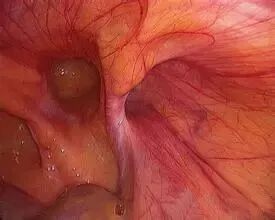

从腹腔里面看是这样的:

图片